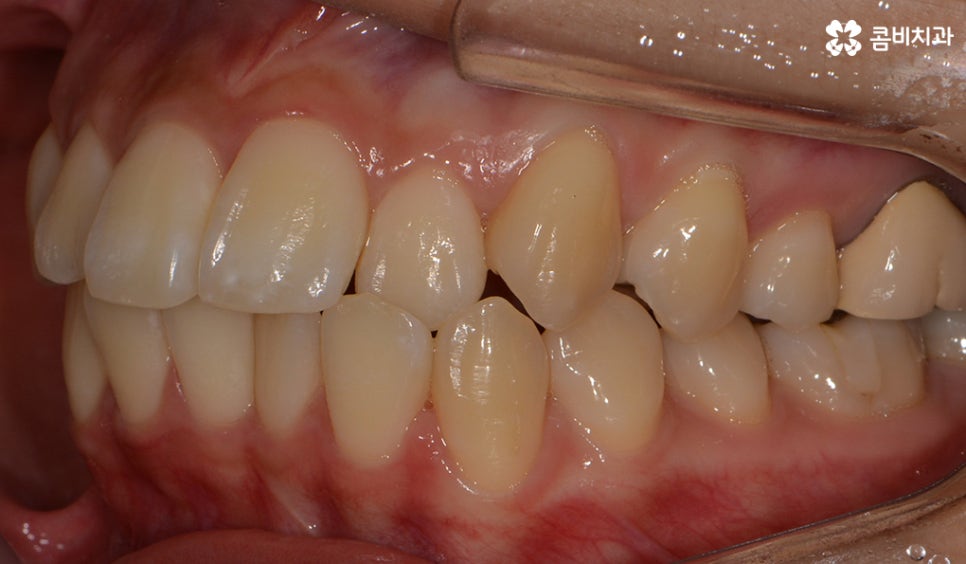

윗니가 설측으로 시술이 진행되고 있는 모습이며

발치를 한 부위 안쪽으로 치아가 이동하기 때문에

돌출입의 개선이 함께 이뤄지며 치열뿐 아니라

얼굴과 자연스럽게 어울리는 결과를 얻을 수 있습니다.

초기에 시술이 진행된 모습에 비해서 윗니가 가지런해졌고

돌출되었던 치아가 안쪽으로 많이 들어온 모습입니다.

발치를 했던 부위가 어딘지 잘 모를 정도로

윗니가 안쪽으로 들어와서 가지런하게

치열이 자리 잡고 있는 모습입니다.